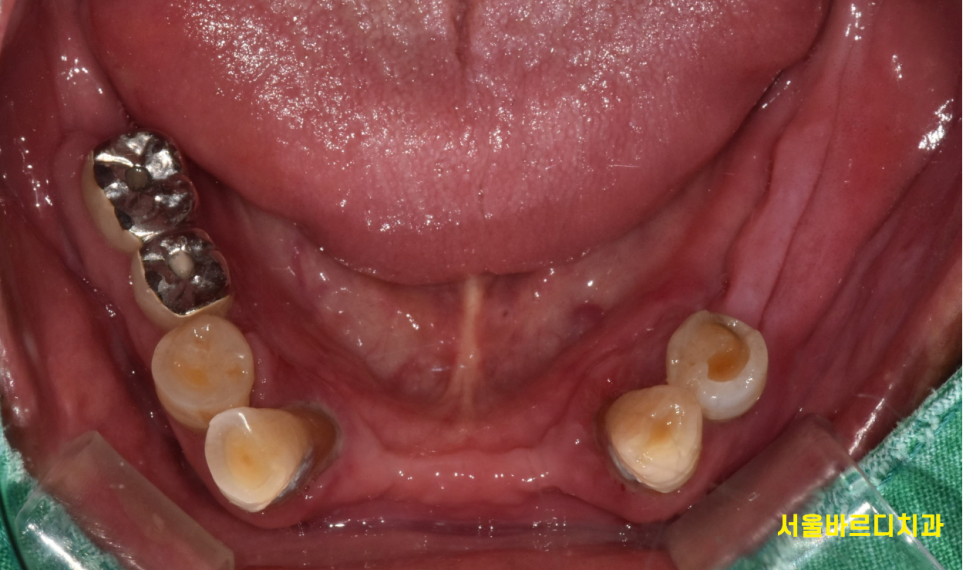

아래 치아를 볼까요?

230725

튼튼한 턱뼈를 가진 아래 치아는 그나마 상태가 양호하네요.

충치 치료를 통해

최대한 살려보아야겠습니다.

아래 치아가 이렇게 많이 썩었는데..

안아프시답니다.

급한 부분이 많아

후순위로 치료하기로 하고...